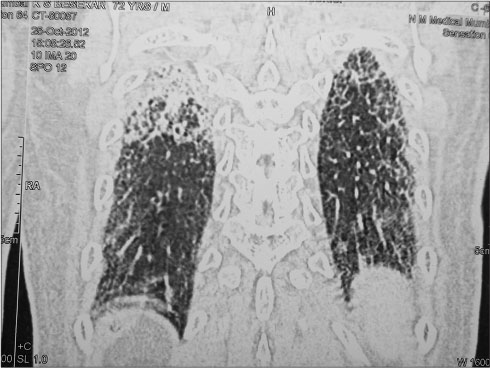

CT scans of the chest and radiograph of the chest [Figures 1], [2], [3] showed inter- and intralobular septal thickenings in the bilateral lung parenchyma predominantly in the lower lobes with peribronchial and fissural nodularity, suggestive of either sarcoidosis or ILD. The patient had a history of chronic cough till few months back which was self-limiting. There was no history of breathlessness, and he was moderately physically active before the present episode. His serum calcium and angiotensin-converting enzyme levels were normal, thus excluding sarcoidosis.

| Figure 3 Pretreatment computed tomography scan chest, lateral sagittal view